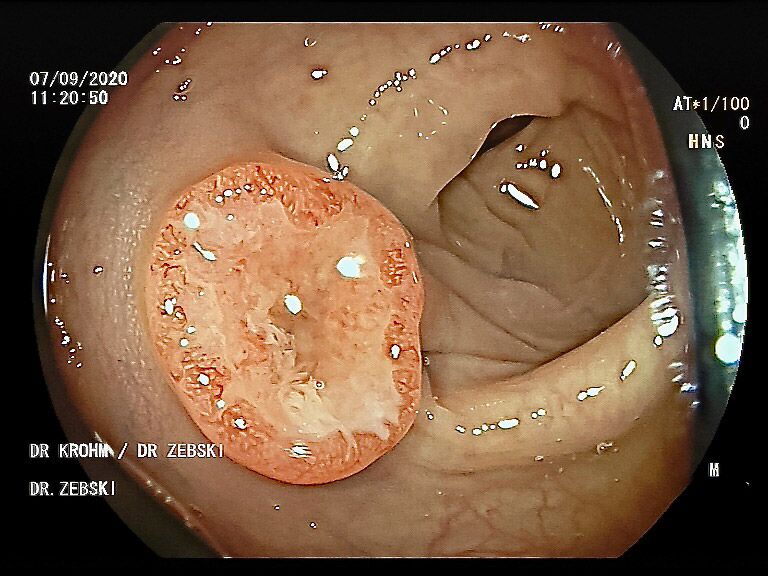

Die Darmspiegelung hilft, dass Darmkrebs gar nicht erst entstehen kann. Denn während der Untersuchung werden auch Polypen entfernt, aus denen sich der Darmkrebs in der Regel entwickelt. Von allen Maßnahmen zur Früherkennung dieser Polypen besitzt die Koloskopie die höchste Empfindlichkeit. Sie weist kleinste Polypen, aber auch Darmkrebs nach, der noch keinerlei Symptome macht. Die Abtragung dieser Polypen erfolgt direkt, wenn sie entdeckt werden. Das geschieht völlig schmerzfrei. Durch die Abtragung der Polypen kann die Entstehung von Darmkrebs effektiv verhindert und die krebsbedingte Sterblichkeit gesenkt werden.